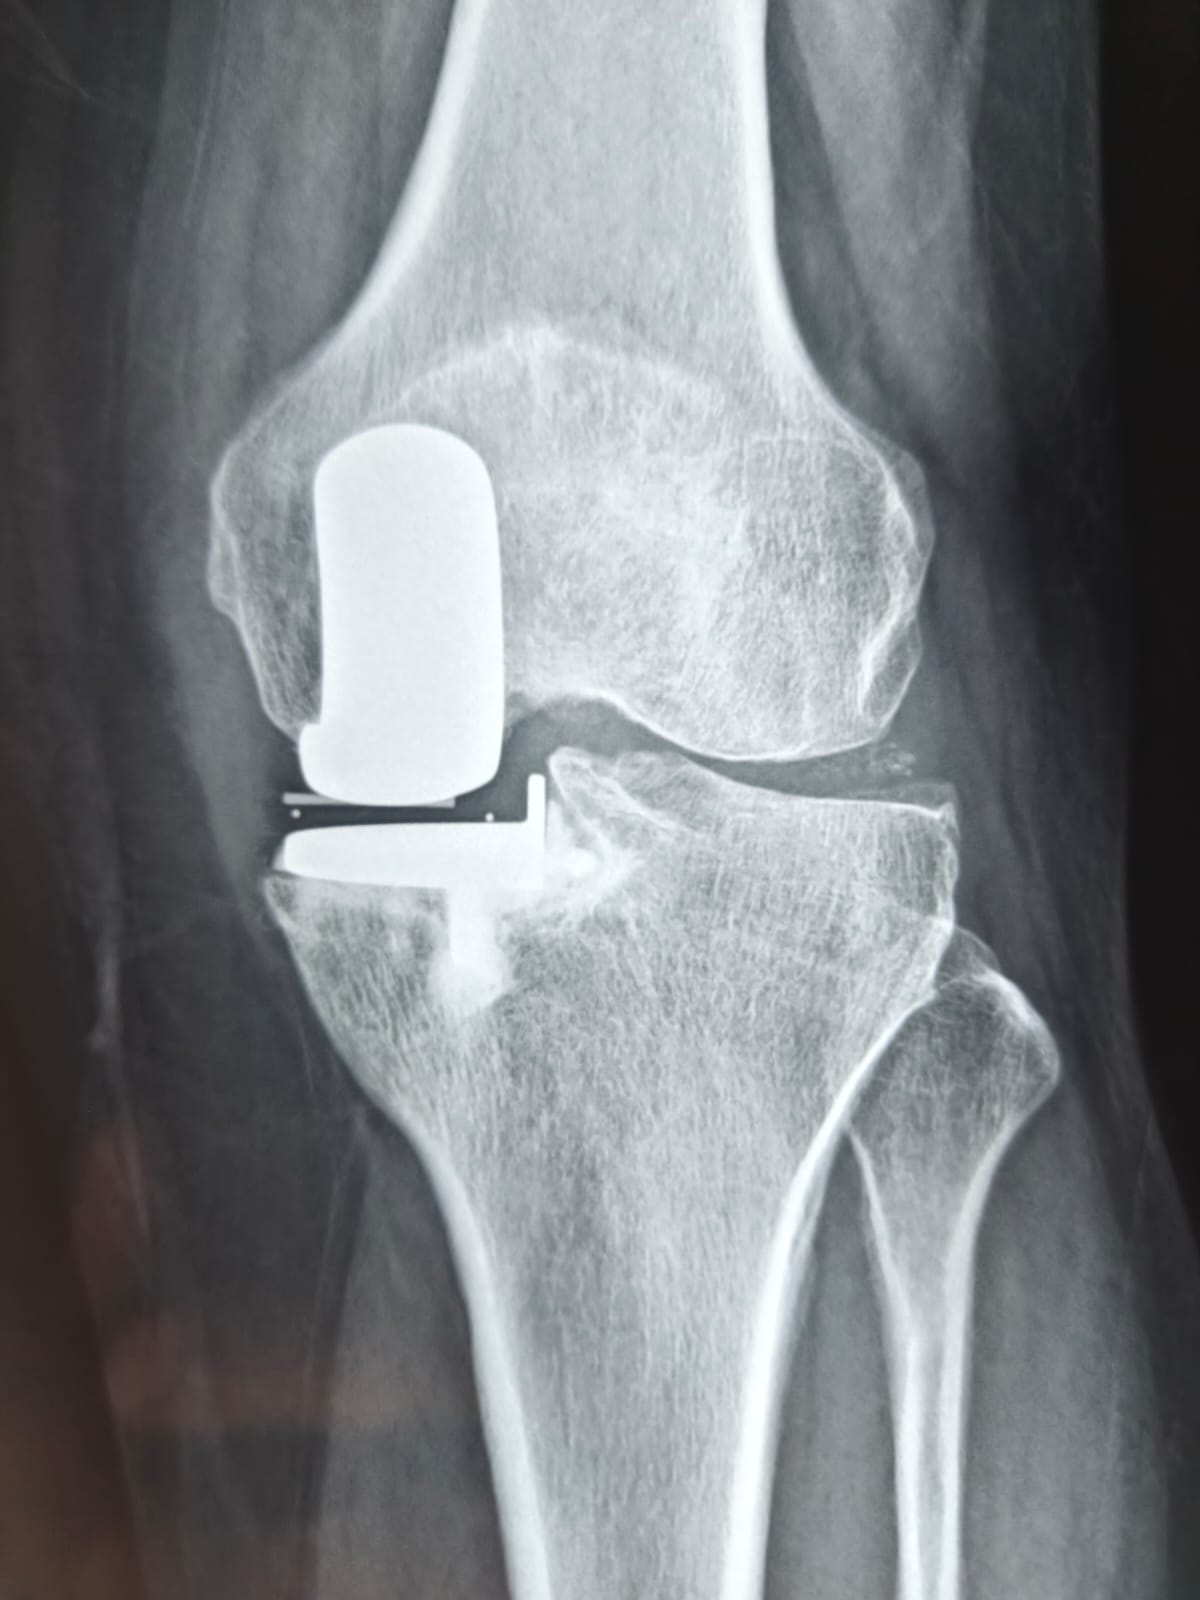

Partial knee replacement (PKR), also known as unicompartmental knee arthroplasty (UKA), is a minimally invasive surgery that helps individuals suffering from knee arthritis or injury regain mobility and reduce pain. After undergoing such surgery, one of the common questions that patients ask is whether they can return to their normal activities — specifically, whether they can sit cross-legged, a posture that is important in many cultures and daily routines.

Partial knee replacement is a procedure designed to relieve pain in the knee joint due to arthritis, fractures, or other knee conditions. Unlike total knee replacement, where the entire knee joint is replaced, partial knee replacement only addresses the damaged portion of the knee. This is ideal for patients whose arthritis is confined to a single compartment of the knee, usually the medial (inner) or lateral (outer) compartment, or the patellofemoral joint (involving the kneecap).